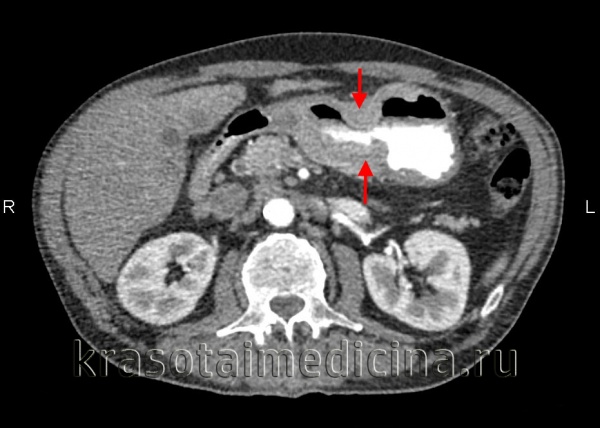

Необходима консультация эндоскописта для визуализации опухолевого процесса и назначения эзофагогастродуоденоскопии и эндоскопической биопсии. Проведение морфологического исследования дает возможность установить правильный диагноз и вовремя начать лечение в 95% случаев. Для уточнения распространенности конгломерата опухоли, степени поражения окружающих органов и наличия метастазов может быть проведено УЗИ, КТ и КТ органов брюшной полости. Клинические и биохимические анализы позволяют оценить общее состояние пациента, степень опухолевой интоксикации.

КТ органов брюшной полости. Злокачественная циркулярная опухоль стенки тела желудка.